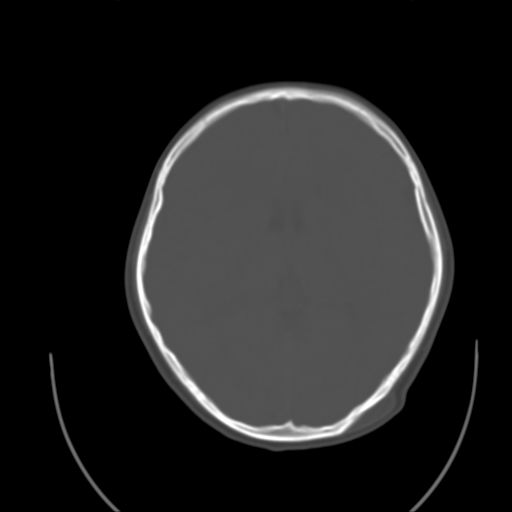

标题: PED1738:男 9岁左枕部包块。 [打印本页]

标题: PED1738:男 9岁左枕部包块。

左枕部头皮下血肿,有外伤史吗?

左枕部皮下软组织密度增厚影---考虑-----左枕部头皮下血肿

考虑皮样囊肿可能性大

皮样囊肿?皮下脂肪瘤?

请提供软组织窗及ct值。